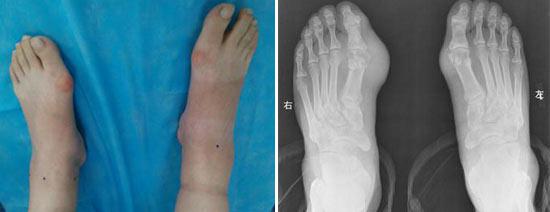

(图:董老先生来院检查显示双脚脚趾关节处痛风石明显,出现活动障碍)

六年前,董老先生刚患痛风时,被误诊为风湿性关节炎,治了很久不见好转,反而更加严重。所以就换了一家医院看诊,经过验血和X光拍摄医生确诊是痛风。但是由于前期的误诊,延误了急性痛风初期的治疗,痛风更加严重。后来又换了好几家医院,都只是给他开一些西药,如秋水仙碱、苯溴马隆之类的,痛风总是好了又反复,反反复复,而且发作次数越来越频繁,病情也更加严重,让董老先生很苦恼。六年间,董老先生遭受痛风反反复复的折磨,发作严重时关节严重畸形,连站立走路都成问题,就别说干别的了。